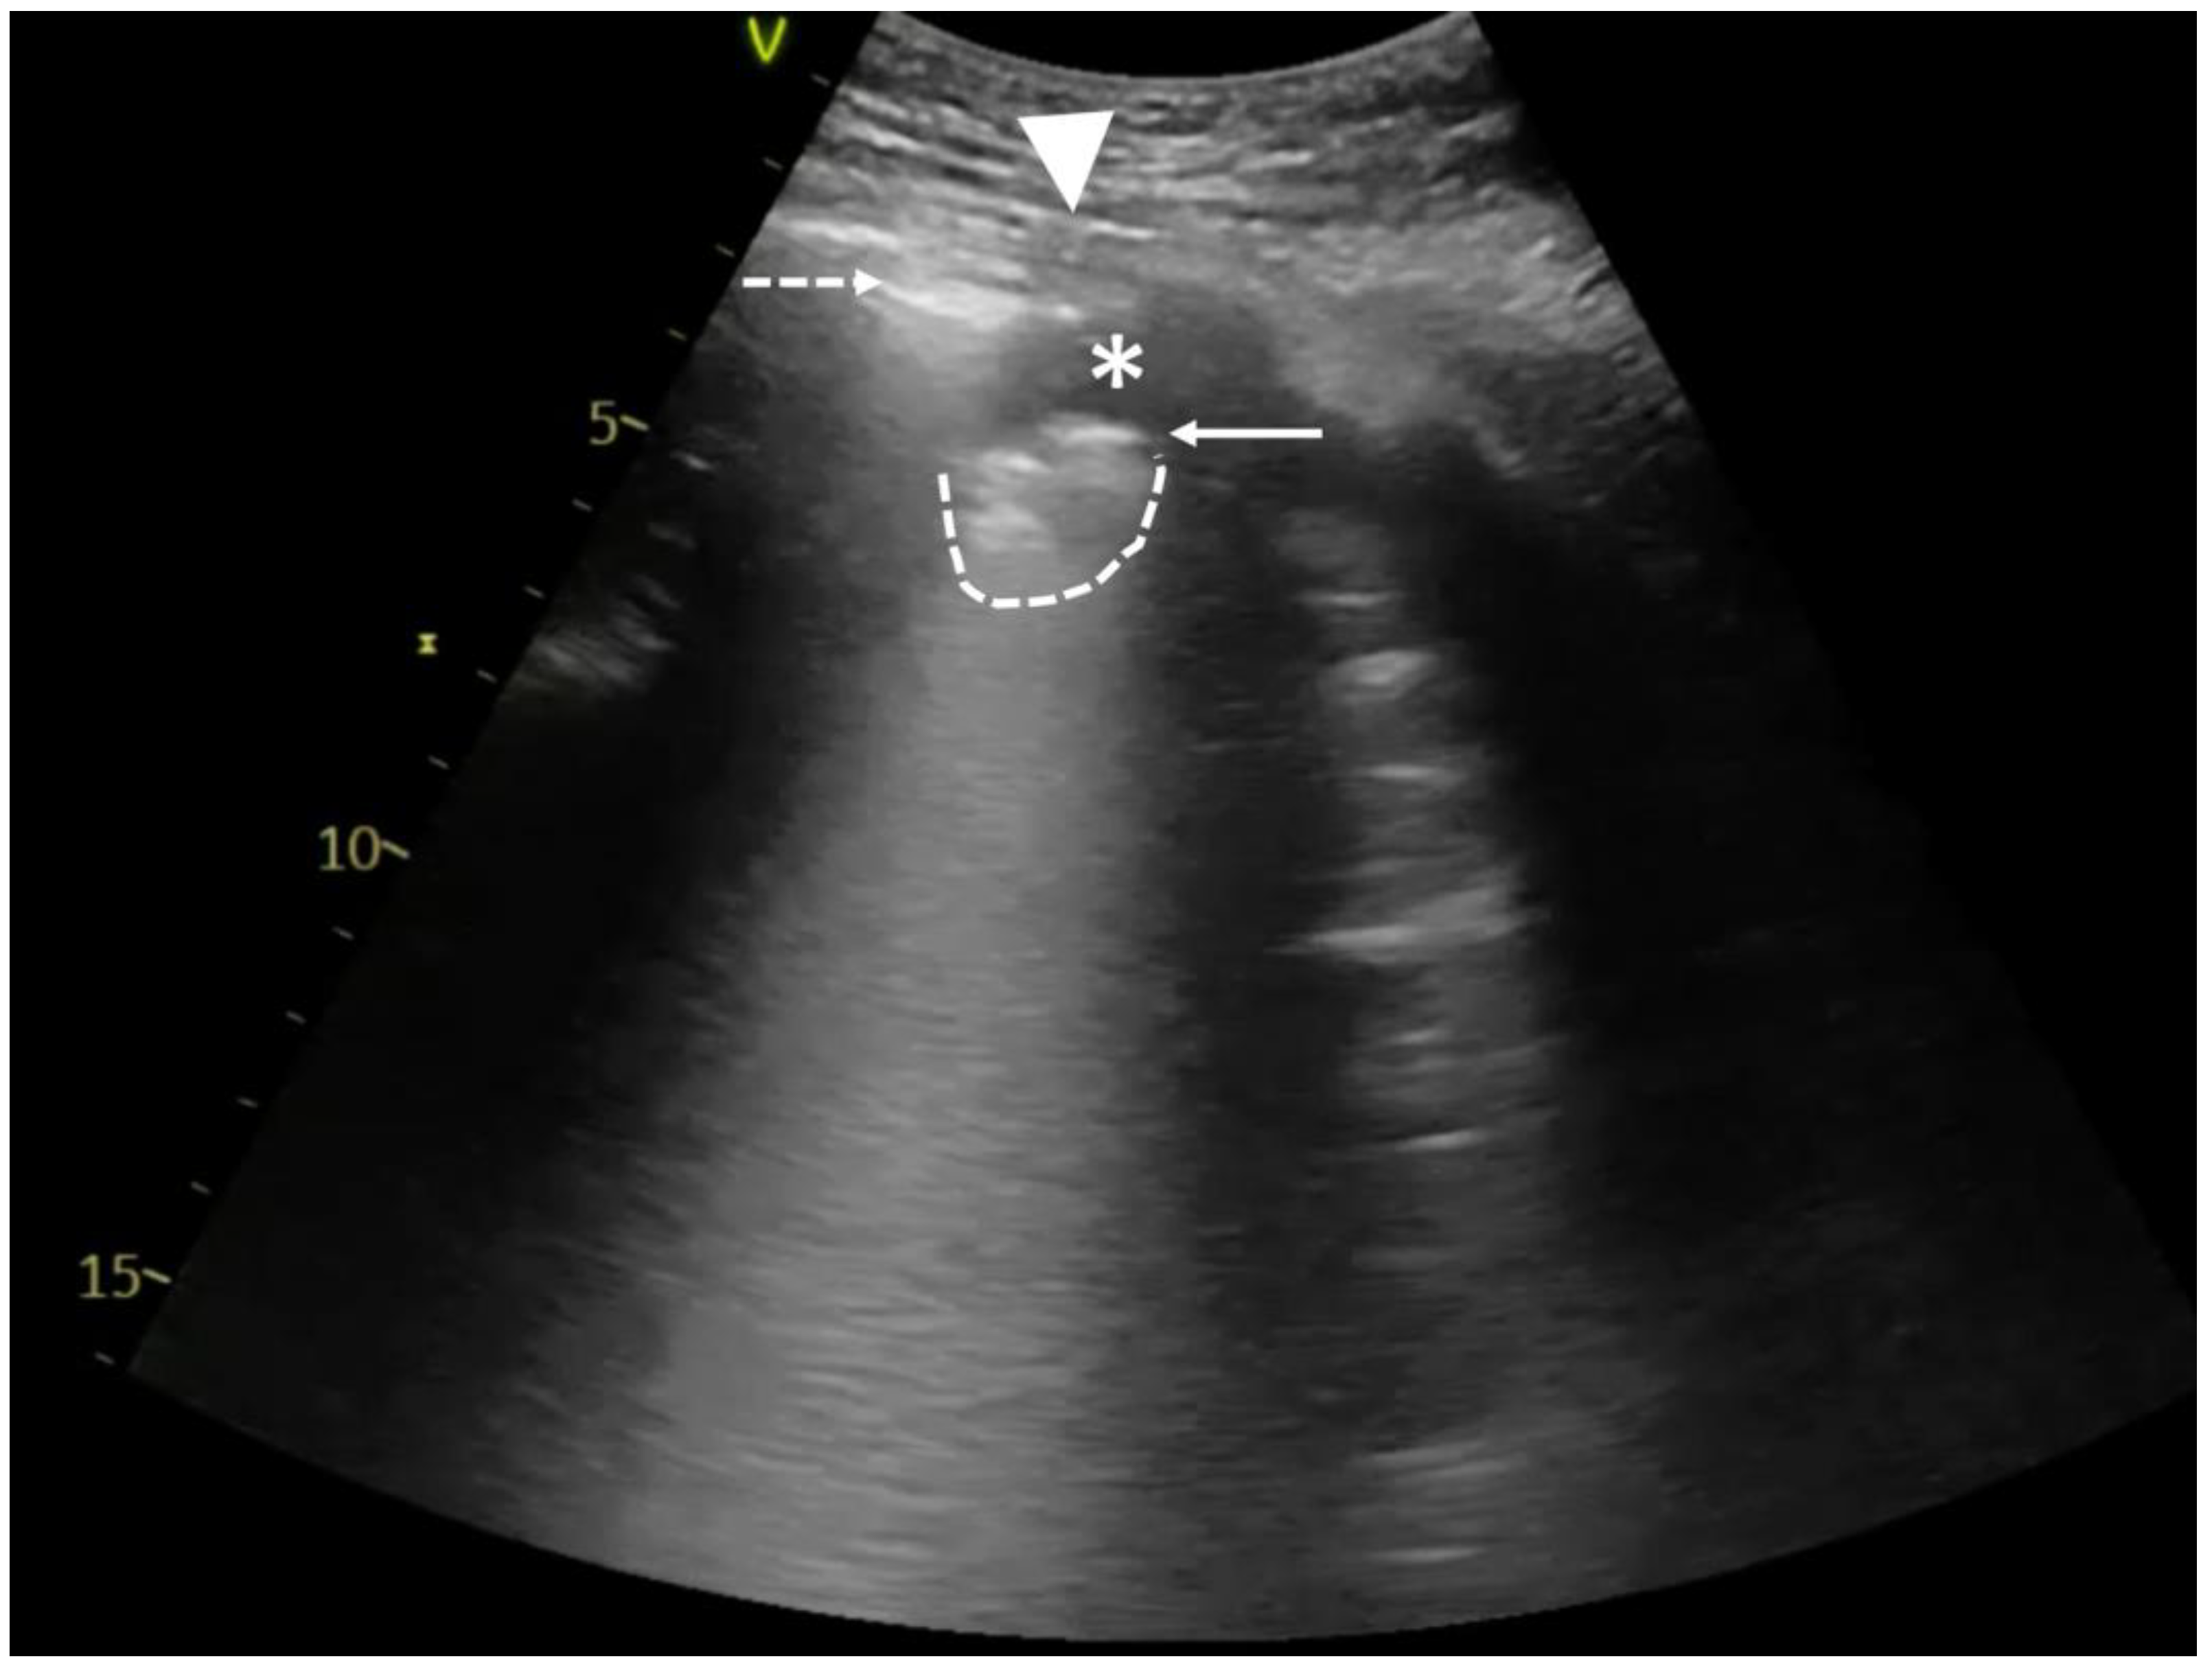

In hydropneumothorax, a typical lung point (Figure 1B; Video S1B) should be distinguished from a sign called the hydro-point (Figure 2; Video S2), where the air/fluid border appears as the interposition between an anechoic space and a non-sliding A-pattern [4]. The observed phenomenon resembles a curtain sign, but unlike the typical one, it can be seen in various areas of the chest wall, not only the base. Also, searching for the lung point can be difficult, time-consuming, or even impossible when the whole lung is collapsed.

Figure 2.

Point-of-care LUS of a 59-year-old smoker with COPD and severe ARDS. LUS was obtained with 1.8–6 MHz convex probe during vv-ECMO therapy and baby lung ventilation (Bilevel; FiO2 40%; PL10 cmH2O; PH 5 cmH2O; Vt~100–150 mL). Considering the LUS images obtained in the previous days (bilateral consolidations), the A-profile on the left side of chest wall was unusual. A careful assessment with LUS revealed the hydro-point, where a pleural effusion in the left pleural cavity coexisted with pneumothorax. Pneumothorax is present on the left side of the image with a blurred line of the parietal pleura (dashed arrow), and no horizontal reverberations developed at the air/tissue boundary. On the right side of the image, fluid in the pleural cavity (asterisk) and irregular, fragmented pleural line (solid arrow) with the subpleural consolidation (dashed line) can be observed. The contact point of both is called hydro-point (triangle), one of the non-typical LUS images confirming the presence of pneumothorax. This dynamic sign, occurring suddenly and transiently on the ultrasound image, can be seen in Video S2.

The following are available online at https://www.mdpi.com/article/10.3390/diagnostics14020206/s1, Video S1A. A 59-year-old male with ARDS, mechanically ventilated (Bilevel; FiO2 60%; PL10 cmH2O; PH15 cmH2O). Point-of-care LUS using a 1.8–6 MHz convex probe in B-mode shows extensive intercostal muscle (ICM) contraction, questionable pleural sliding (arrow), and horizontal reverberation artifacts formed on the air/tissue boundary (dashed arrow). In M-mode, a barcode sign with vertical artifacts is observed (asterisk). Unlike a real lung pulse, the artifacts originate from the intercostal muscles, above the pleural line. Video S1B. Point-of-care LUS using a 1.8–6 MHz convex probe. On the left side of the LUS image, pneumothorax is visible with abolished lung sliding (dashed arrow) and no vertical reverberation artifacts. A part of the lung with fragmented pleural line (arrow) and subpleural consolidation (dashed line) appears suddenly and transiently on the right side of the ultrasound image. The contact area is called the lung point (triangle). Video S2. A 59-year-old smoker with COPD and severe ARDS. All pictures were obtained with a 1.8–6 MHz convex probe during vv-ECMO therapy and baby lung ventilation (Bilevel; FiO2 40%; PL10 cmH2O; PH 5 cmH2O; Vt~100–150 mL). On the left side of the LUS image, pneumothorax can be observed, with an irregular line of the parietal pleura (dashed arrow), abolished pleural sliding, and no horizontal reverberations developed at the air/tissue boundary. A cyclically appearing fluid (asterisk) and a lung with a visible irregular pleural line (arrow) and consolidation (dashed line) can be seen on the right side. The contact point of both is called the hydro-point (triangle). Video S3. A 24-year-old male with human immunodeficiency virus (HIV) infection and ARDS due to suspected atypical bacterial pneumonia. Ventilated with guaranteed tidal volume (Bilevel Volume Guarantee; FiO2 100%; Vt 400 mL; PEEP 6 cmH2O; PIP 30 cmH2O). Point-of-care LUS with a 1.8–6 MHz convex probe. Image of blurred and fragmented pleural line (arrow) with visible subpleural consolidations (dashed lines). In addition, coexisting horizontal pleural reverberations (dashed arrow) with abolished pleural sliding and comet tail artifacts (asterisks) most likely emerging from subpleural structures. The image corresponds to the bullous emphysema in the CT scan, as shown in Figure 3B.